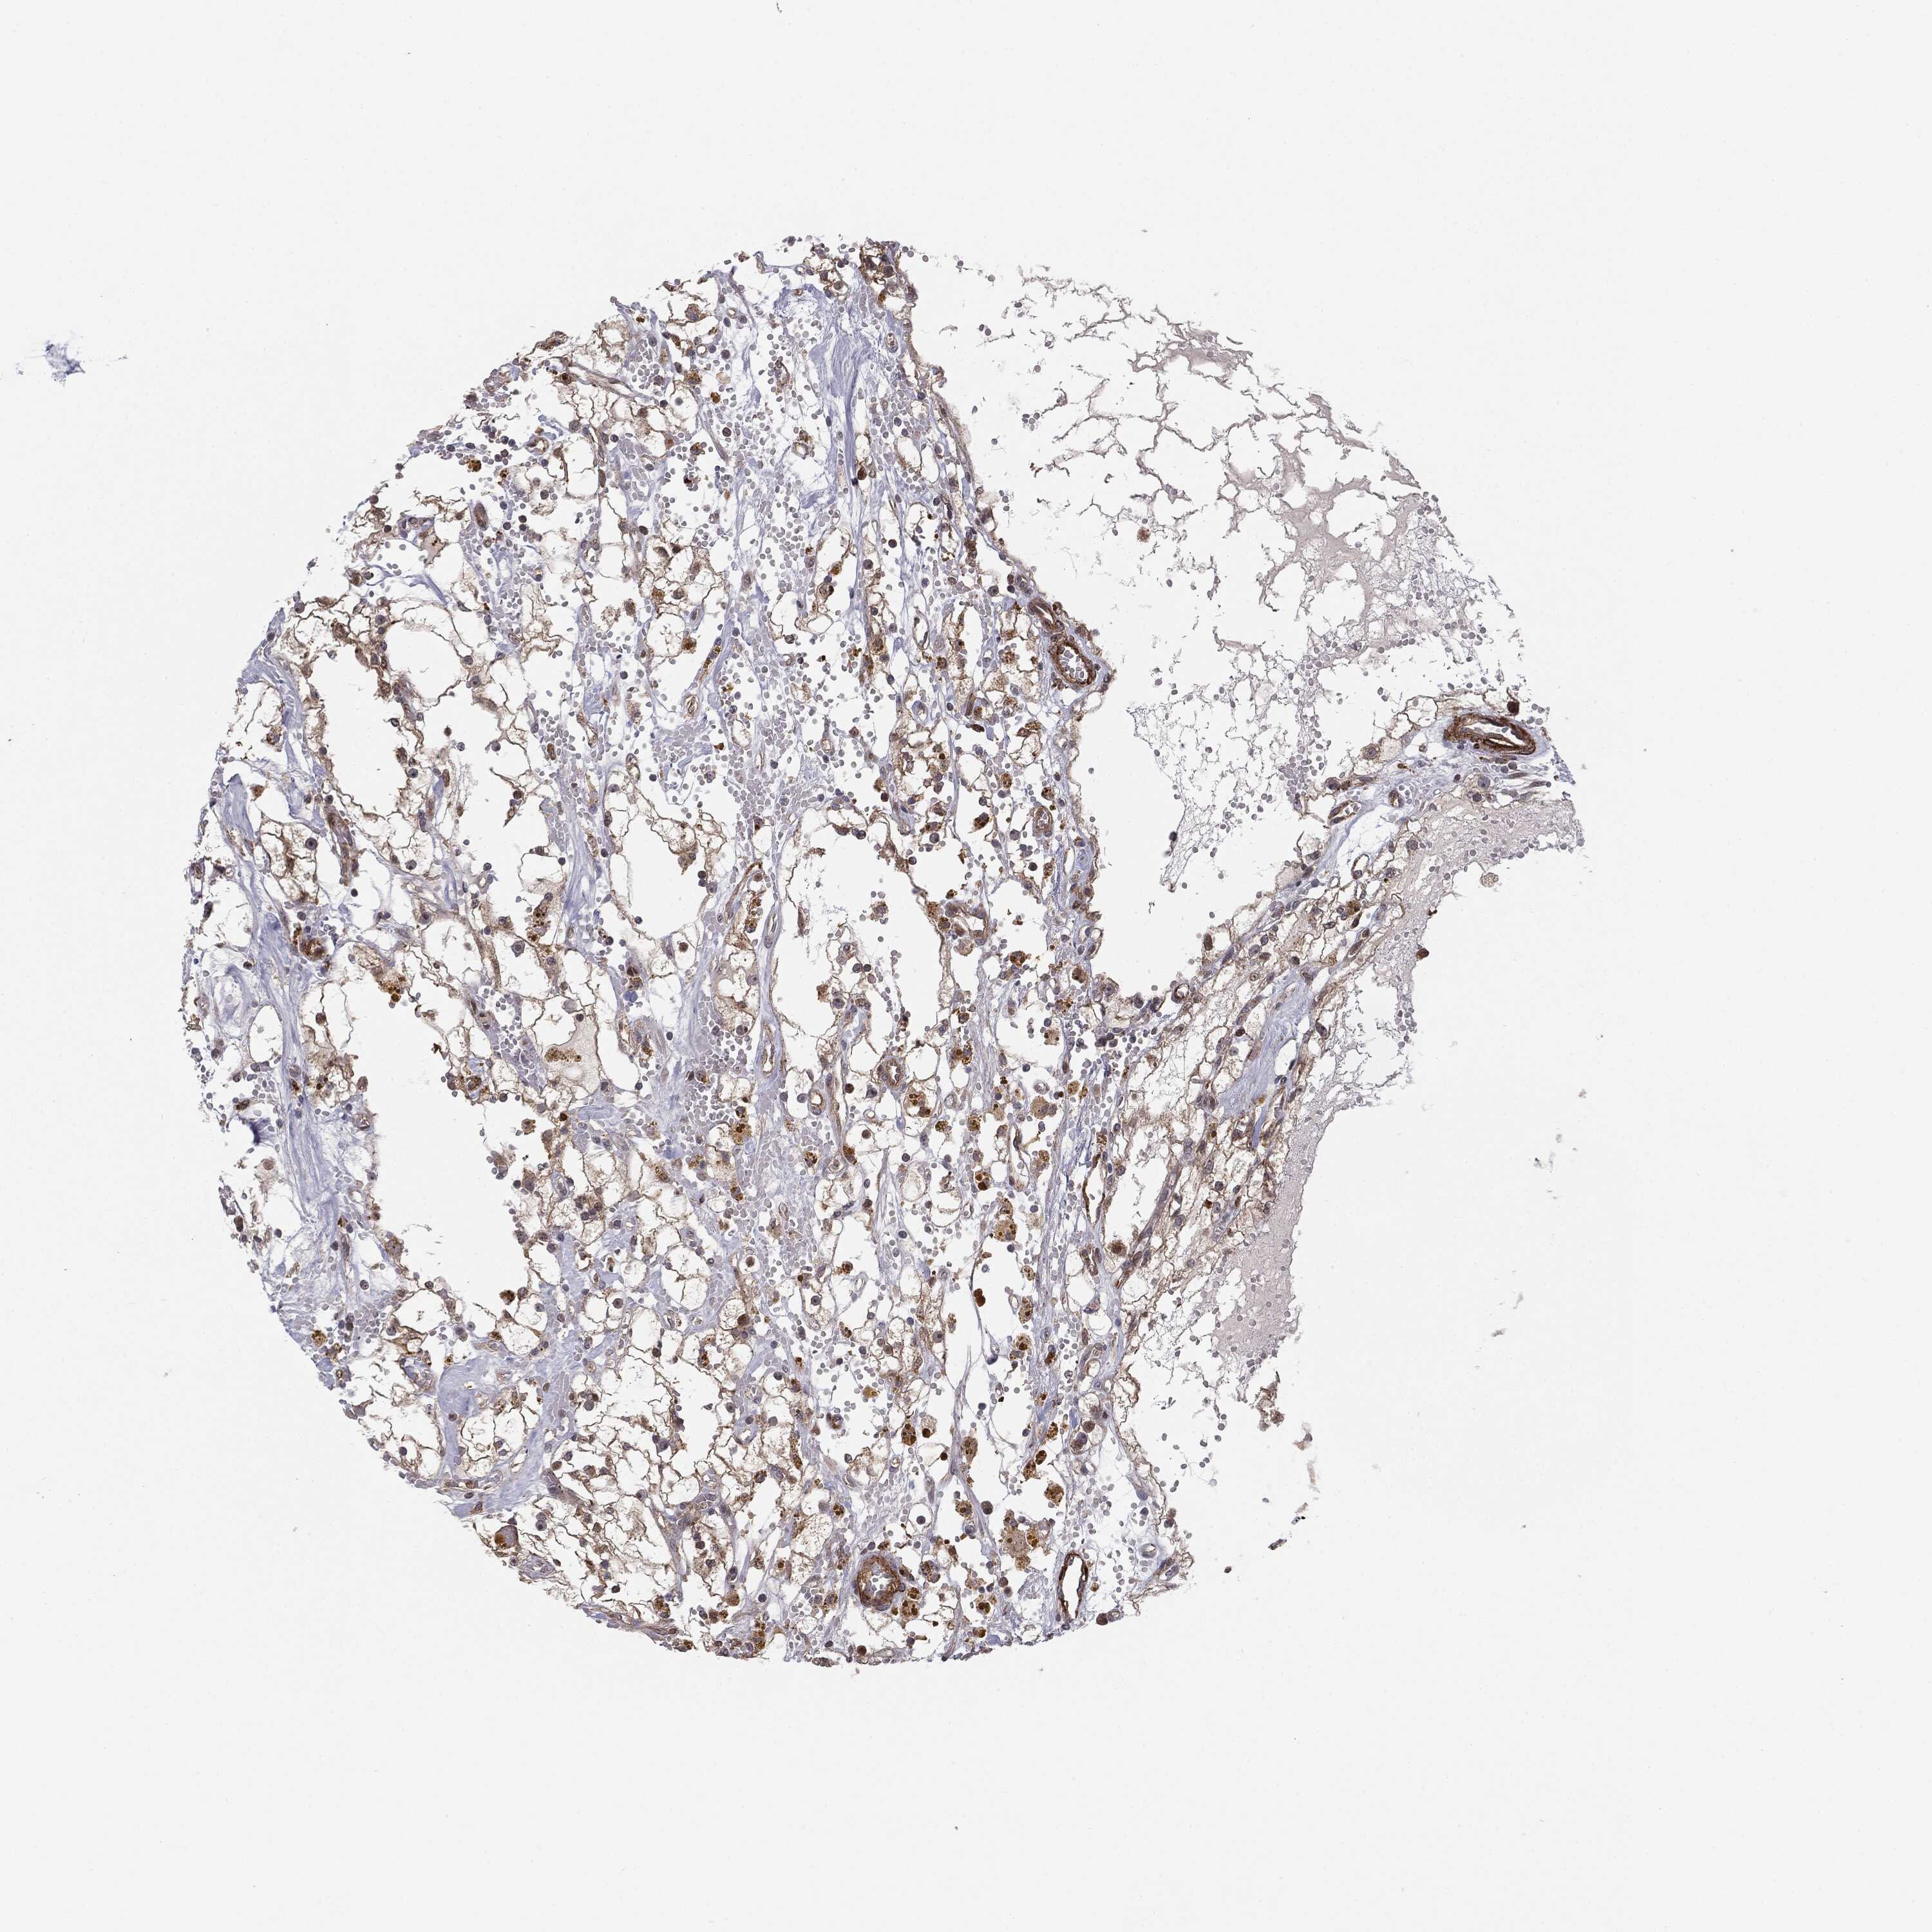

Renal cancer

Kidney renal clear cell carcinoma